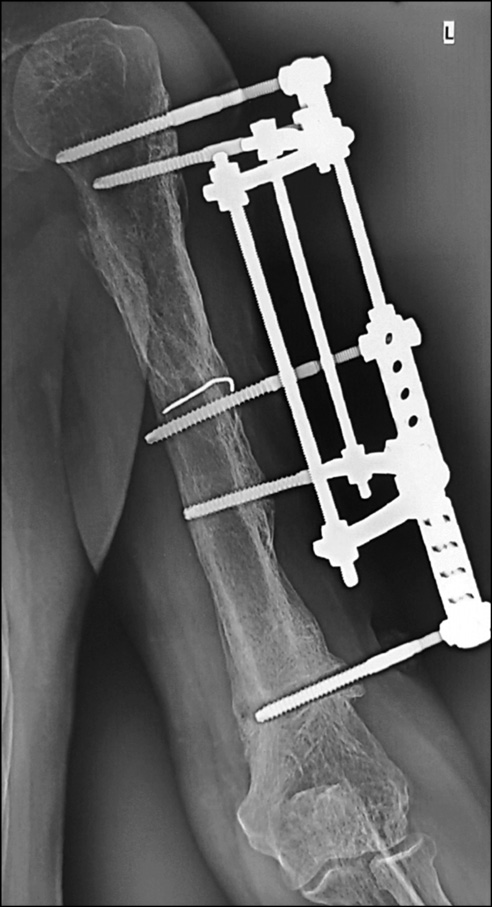

Через 5 мес. при повторном падении пациент получил патологический перелом на границе проксимального и среднего отдела диафиза левой плечевой кости (рис. 6). Госпитализирован в нашу клинику.

Рис. 6. Рентгенограммы левой плечевой кости при поступлении пациента в наше отделение